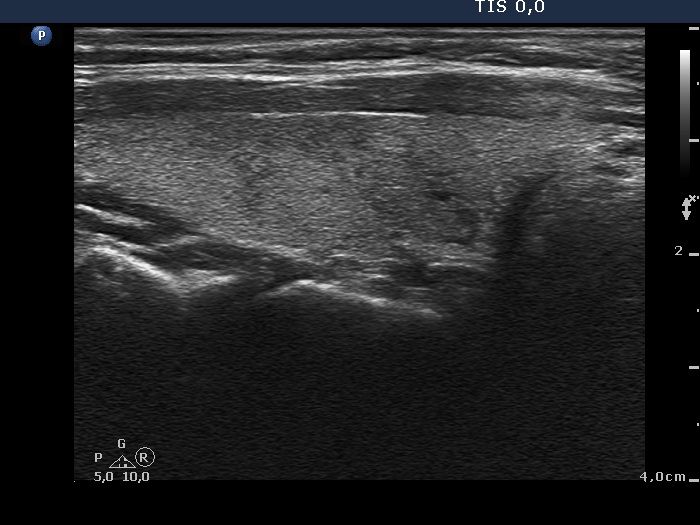

Follow-up investigation 2 months after the first visit (ultrasonographic picture 2)

Right lobe, longitudinal scan. Not only the echogenicity but also the size of the lobe has decreased.